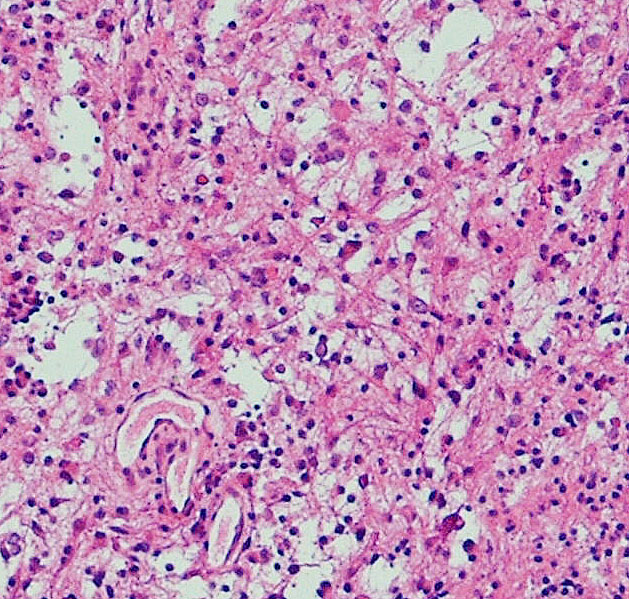

毛様類粘液性星細胞腫の病理像です。関質が広くて粘液用の物質が貯留されています。これは手術で取る時にドロドロの腫瘍に見えますから,ちょっと硬い普通の毛様細胞性星細胞腫とは判別できます。この病理像をもつ腫瘍は,患者さんの年齢が年長児になっていくと,自然に変化して普通の毛様細胞性星細胞腫に変わっていきます。腫瘍も年をとるのだと考えられます。ですから,毛様類粘液性星細胞腫は特殊なものではなくて,毛様細胞性星細胞腫の赤ちゃんです。右側の画像では,血管中心性に腫瘍細胞が配列するangiocentric patternがみられます。